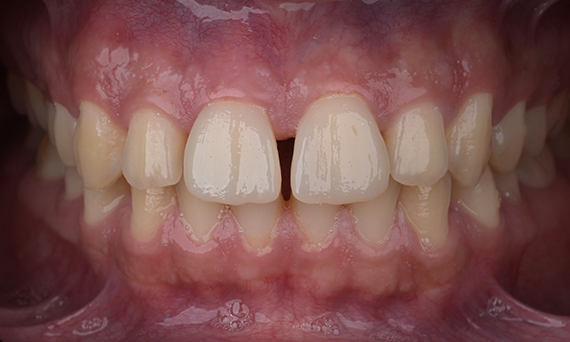

Before: Initial situation prior to orthodontic treatment.

After: Final result, 1 week post-operative.